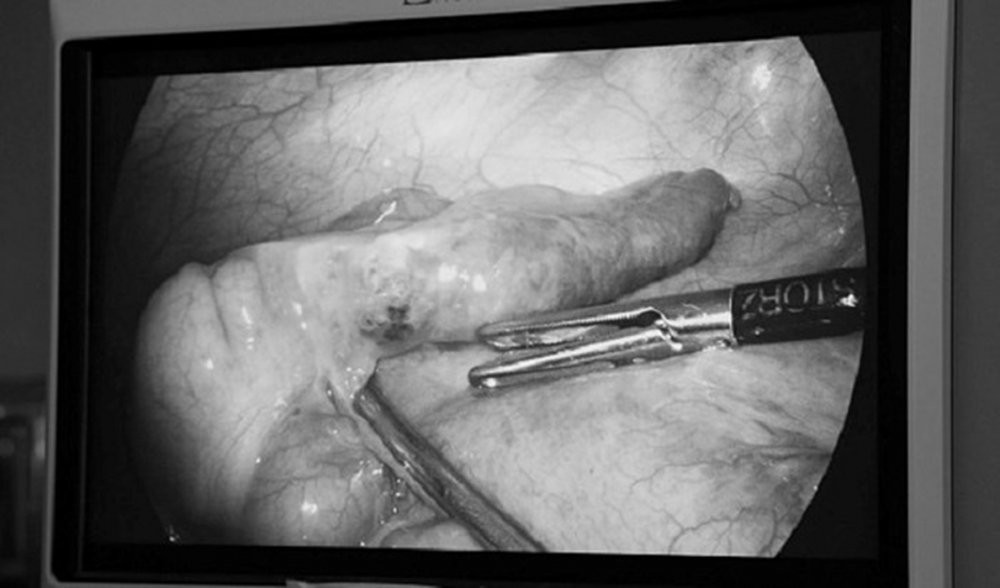

Hình ảnh nội soi gắp dị vật là mảnh xương cá trong ruột của bệnh nhân. (Ảnh: Bệnh viện cung cấp)

Trong quá trình phẫu thuật các bác sĩ ngạc nhiên khi phát hiện 1 mảnh dị vật đâm xuyên thành ruột của bệnh nhân. Đó là một mảnh xương cá có kích thước nhỏ. Bệnh nhân không hề biết điều này. Do mảnh xương ở khá lâu trong bụng nên gây ra tình trạng viêm vùng tấy hố chậu (P) và viêm ruột thừa thứ phát.